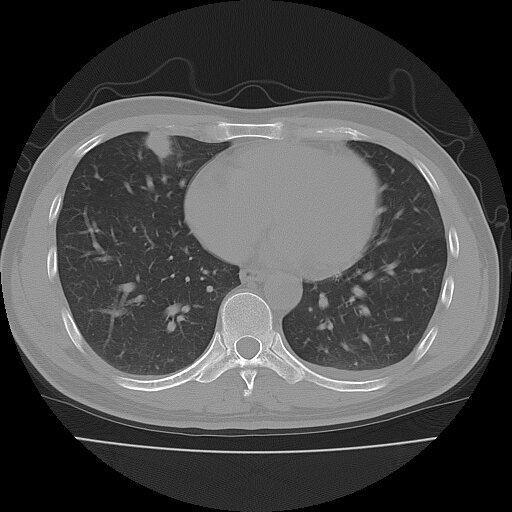

左侧胸痛,无其他病史

考虑肺内炎性肉芽肿,少量胸水。

转移瘤

考虑两肺感染性病变;建议抗炎治疗后复查。

暂考虑两肺感染性病变,左侧少量胸水;建议抗炎治疗后复查

首先考虑双肺感染性病变,左侧少量胸水,见过类似病例,抗炎后都吸收了

右侧胸膜下多发小结节——支持考虑:炎性假瘤!

警惕转移灶